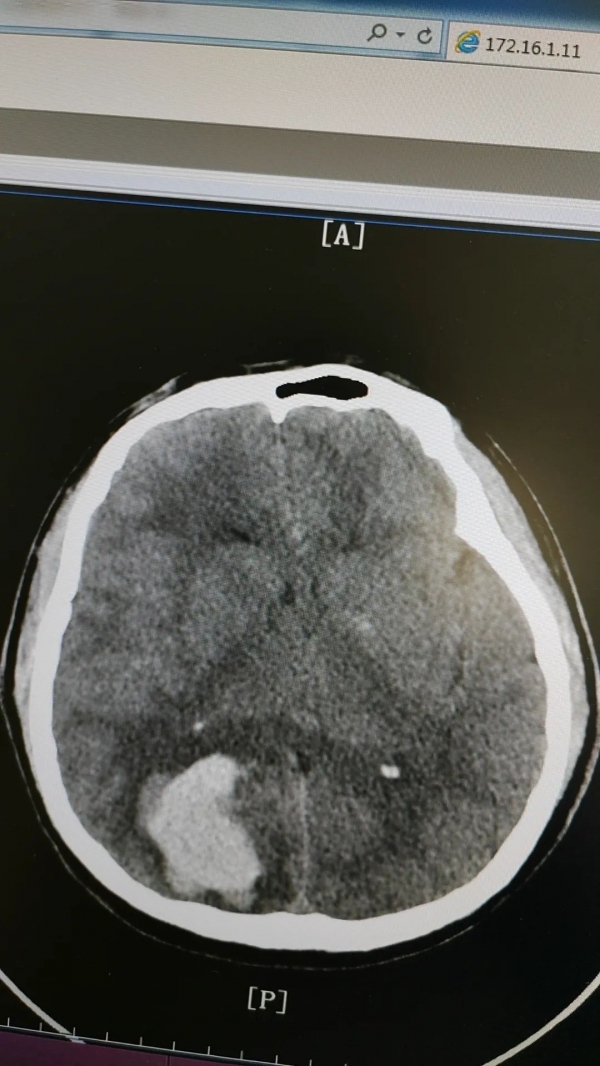

53歲的柴大叔家住湖南長沙,2023年9月工作需要來鄭州出差,出差期間突然頭痛、嘔吐起來,隨即撥打120送至我院急診科,經(jīng)過CT檢查發(fā)現(xiàn),柴大叔右側(cè)頂枕葉腦出血,并有水腫情況,神經(jīng)外科專家張新昌教授立即會診,柴大叔被確診為“腦出血”并收治外一科治療。

腦出血是嚴(yán)重的腦血管疾病,致死率高達(dá)35%以上,易引起偏癱、認(rèn)知障礙、語言障礙等后遺癥。

危急時刻,外一科團(tuán)隊(duì)協(xié)同麻醉科手術(shù)室為核心力量,開通綠色通道,各科室部門快速響應(yīng)整合協(xié)作,制定科學(xué)且可行的方案,全力以赴展開救治。

術(shù)前

術(shù)后